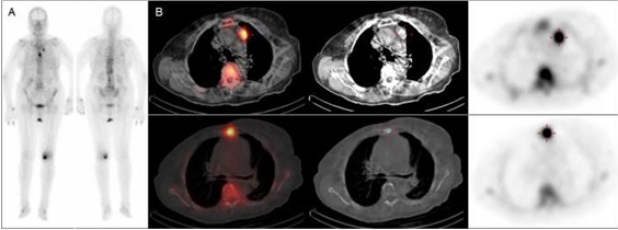

Mujer de 89 años diagnosticada de carcinoma mucinoso de mama izquierda estadio IIB (T2 N1 M0), tratado con cirugía más linfadenectomía axilar. Histológicamente, existía estroma mucoide en el tumor y sustitución masiva metastásica mucosecretora en ganglios axilares. Tras la radioterapia continúa seguimiento con remisión completa. A los seis años presenta elevación del antígeno carcinoembrionario (CEA), astenia y dolor en dorso. Es remitida al Servicio de Medicina Nuclear para descartar afectación ósea secundaria. La gammagrafía con 99mTc-HDP presenta un depósito en el esternón sugerente de malignidad y otro foco paraaórtico izquierdo, de difícil caracterización. El SPECT-TC de tórax localizó correctamente la captación sobre un nódulo mediastinal (fig. 1). Posteriormente, se realizó un PET-TC con 18F-FDG para re-estadificación, evidenciando compromiso metastásico óseo y ganglionar mediastinal (fig. 2).